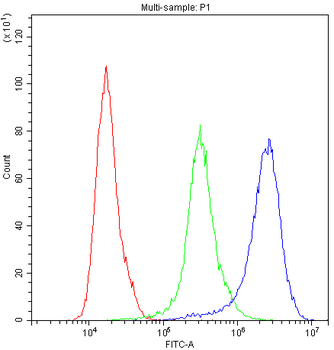

Anti-Cyclophilin A/PPIA Antibody [orb19174]

FC, ICC, IF, IHC, IHC-Fr, WB

Human, Mouse, Rat

Rabbit

Polyclonal

Unconjugated

10 μg, 100 μgCYPA Rabbit Polyclonal Antibody [orb100498]

FC, IF, IHC-Fr, IHC-P, WB

Bovine, Canine, Porcine, Rabbit

Human, Mouse, Rat

Rabbit

Polyclonal

Unconjugated